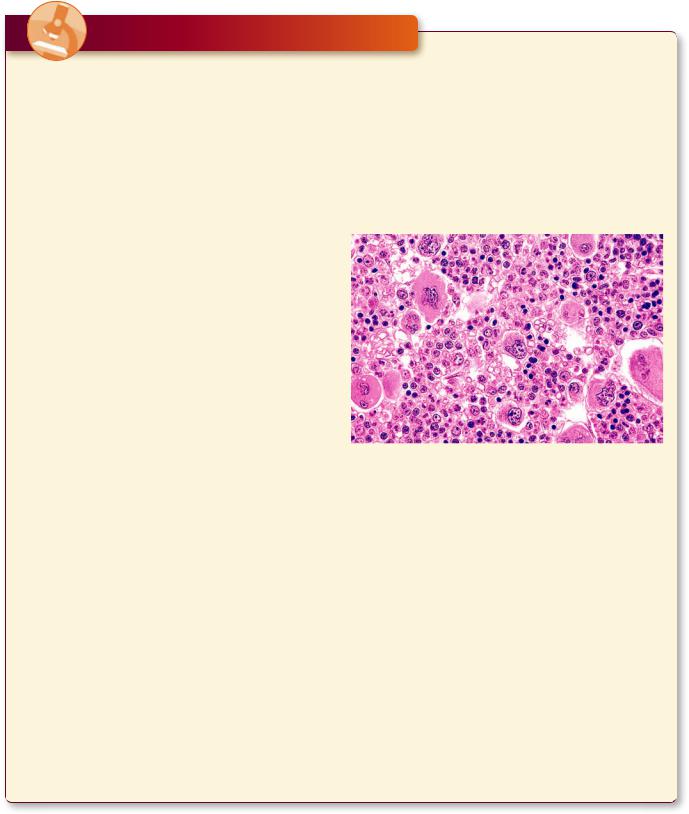

Multiple Myeloma

Polycythemia Vera

Polycythemia vera (primary polycythemia) is a rare disorder of the blood that manifests itself by an excess production of red blood cells and, frequently, platelets, resulting in greater blood volume and an increase in the viscosity of blood. It mainly involves individuals who are in their early sixties, although occasionally it occurs in patients who are in their early twenties. Symptoms

may be absent for a number of years after the onset of the condition, but patients suffering from this disorder may exhibit headaches, vertigo, fatigue, shortness of breath, enlarged liver and spleen, burning sensation in the extremities, visual disorders, as well as gingival bleeding, and generalized itching. If left untreated, the patient may die within 2 years, but with proper treatment, the lifespan can be extended by 10 to 20 years.

This is a bone marrow biopsy from a middle-aged woman suffering from polycythemia vera. Observe that the marrow is hypercellular exhibiting an abnormally high number of erythrocyte precursors and megakaryocytes. (Reprinted with permission from Mills SE, Carter D, Greenson JK, Reuter VE, Stoler MH eds. Sternberger’s Diagnostic Surgical Pathology, 5th ed. Philadelphia: Lippincott Williams & Wilkins 2010. p. 635.)